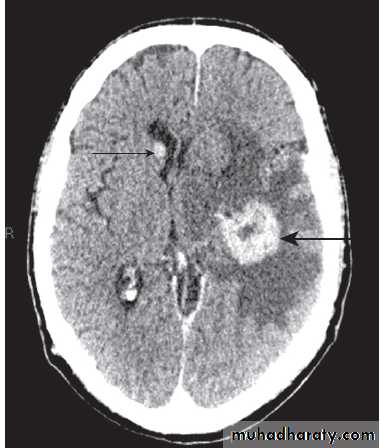

Fig. Different techniques of imaging the head and brain. A Skull X-ray showing lytic skull lesion (eosinophilic granuloma – arrow). B CT

showing complete middle cerebral artery infarct (arrows). C MRI showing widespread areas of high signal in multiple sclerosis (arrows). D SPECT after

caudate infarct showing relative hypoperfusion of overlying right cerebral cortex (arrows).